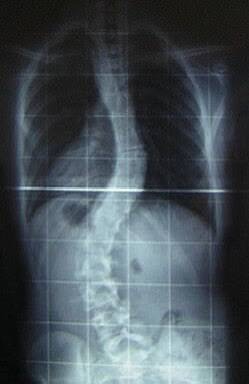

أثناء التقييم الشامل قبل الجراحة، تم اكتشاف وجود جنف صدري قطنيمتقدم لم يكن المريض على علمٍ به. وبعد المناقشة الطبية، تقرر البدء بعمليةتصحيح العمود الفقري كخطوة أولى.

أُجريت العملية بنجاح رغم خطورتها، وشهدت فترة النقاهة مضاعفات تمثلت بفقدان دم شديد تطلب نقل وحدات دموية وتأخر النهوض والحركة لمدة تسعة أشهر تقريباً.

عند التعافي، أظهرت الصور الشعاعية تحسناً واضحاً في استقامة العمودالفقري وتوازناً في القوام العام. لاحقاً، أُجريت جراحة ثانية لتصحيح التقعرالصدري مع وضع صفيحة معدنية مؤقتة تمت إزالتها بعد عام، وكانت النتيجةالتجميلية والوظيفية مرضية للغاية